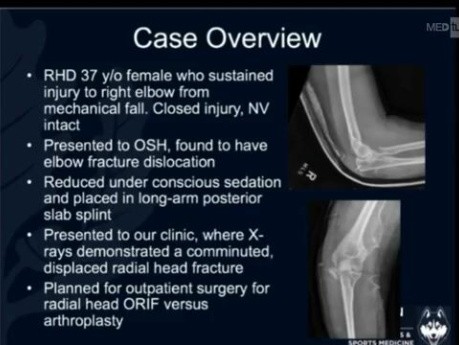

Fractures de l'Humérus

Niel Kang parle des fractures de l'humérus.Veuillez nous suivre sur Twitter, Facebook, Instagram, LinkedIn et Telegram. Notes orthopédiques concises – Livre de préparation aux examens primé : https://orthopaedicacademy.co....

OrthoProcédure - Arthroplastie de la Tête Radiale

OrthoProcédure - Arthroplastie de la Tête Radiale.

MedSchoolCoach

institution commerciale